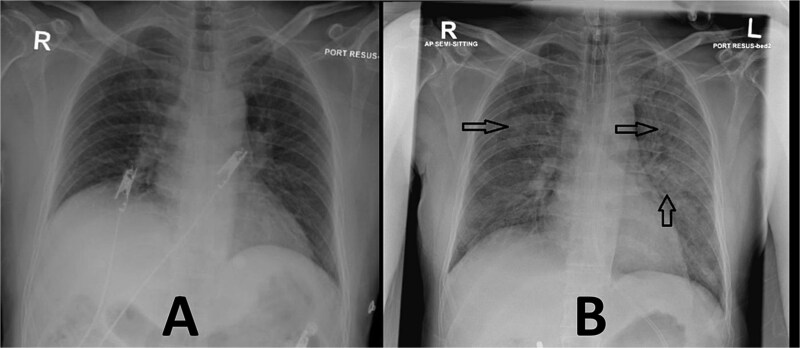

氯胺酮在急诊科的使用比以往任何时候都更广泛,因为它具有良好的安全性和镇痛和麻醉的综合特性。它通过交感神经系统刺激心血管系统的能力尤其重要,因为患者可能出现血流动力学不稳定。然而,由于极度心动过速和严重的全身血压升高,人们仍然担心心脏功能失代偿的风险。在本病例中,一名已知有冠状动脉疾病和充血性心力衰竭病史的中年男性,在给予氯胺酮镇静后病情明显恶化,以便于进行肺血管造影计算机断层扫描。他出现急性肺水肿和心源性休克,需要机械通气和肌力支持。因此,有潜在心力衰竭的患者慎用氯胺酮。氯胺酮与心脏失代偿导致的心源性休克和肺水肿之间的因果关系有待进一步研究。

Ketamine use in the emergency department is more widespread than ever due to its favorable safety profile and combined analgesic and anesthetic properties. Its ability to stimulate the cardiovascular system via the sympathetic nervous system is particularly important, as patients can develop hemodynamic instability. However, concerns remain regarding the risk of decompensated cardiac function due to extreme tachycardia and severely elevated systemic blood pressure. In this case, a middle-aged male with a known history of coronary artery disease and congestive heart failure deteriorated significantly after ketamine was administered for sedation to facilitate a computed tomography pulmonary angiogram. He developed acute pulmonary edema and cardiogenic shock, requiring mechanical ventilation and inotropic support. Therefore, it is advisable to use ketamine with caution in patients with underlying heart failure. Further research is needed to establish a causal relationship between ketamine and cardiac decompensation leading to cardiogenic shock and pulmonary edema in selected patients.